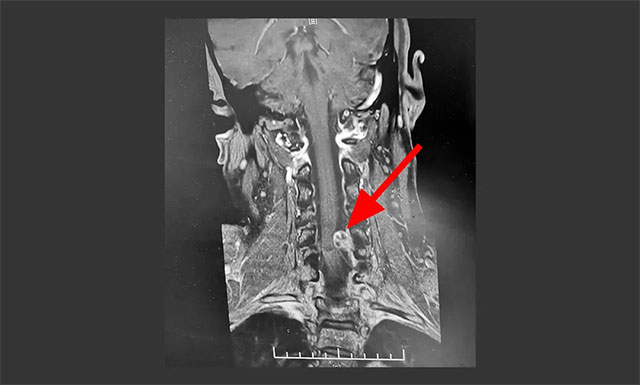

▲ MR顯示腫瘤位于椎管左側(cè)髓外硬膜下

結(jié)合患者癥狀及之前相關(guān)影像檢查,有著多年臨床經(jīng)驗(yàn)的潘仁龍主任懷疑患者可能為脊髓相關(guān)病變。急行頸椎MRI平掃+MRA+MRM示,頸椎序列整齊、曲度存變直;平頸5椎體水平,椎管左側(cè)髓外硬膜下見(jiàn)一“啞鈴狀”異常信號(hào)灶,椎管內(nèi)灶矢橫高徑約8*10*15mm,跨越左側(cè)頸5-6椎間孔向外生長(zhǎng);毗鄰脊髓受壓右偏。頸5-6椎間盤(pán)脊髓變性、伴輕度右后突出;頸3-4、頸4-5椎間盤(pán)變性、膨出;頸椎退行性改變。